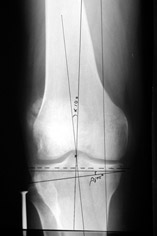

AC> Вот, с учетом и без учета, и на разных уровнях...

Из приведнной схемы не совсеим понял что означают разноцветные линии.

a> Из приведнной схемы не совсеим понял что означают разноцветные линии.

Черные - это нынешняя механическая ось. Красные - это планируемая правильная ось.

;-) Читайте Палея. Стр. 114-115.

a> Я всегда делаю медиализацию. См схему. И для данного случая

Медиализация - это чисто эстетический прием, как я понимаю. Поскольку если делать остеотомию ниже вершины деформации, для восстановления оси надо делать смещение по ширине, в данном случае как раз латерализацию.

А вот на схемке без осей - там на разных уровнях (который правильнее?) устранение варуса чисто открытым клином без медиализации-латерализации. Если как-то так сделать - этого недостаточно будет?